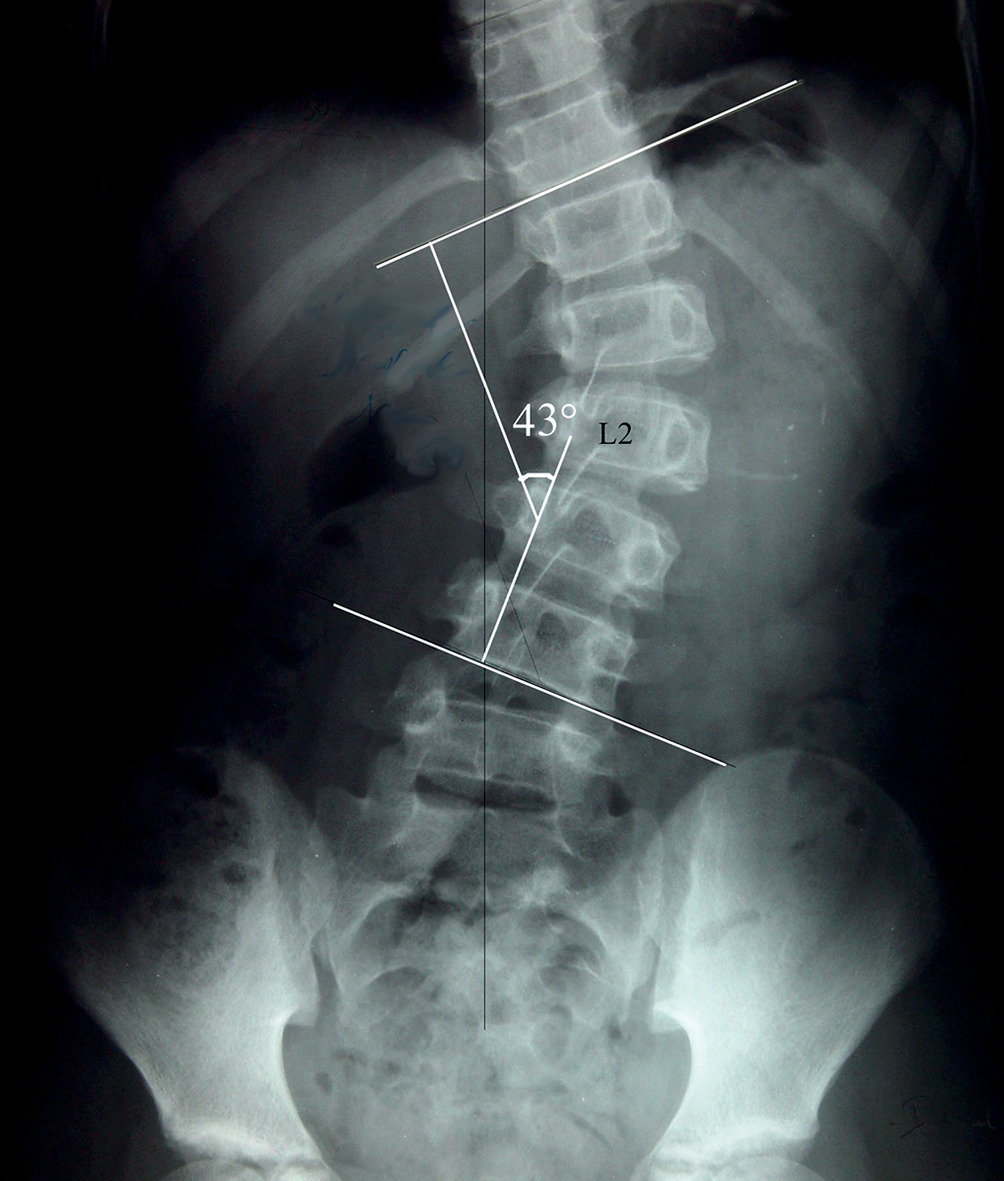

L’angulation dans le plan frontal est appréciée en mesurant l’angle de Cobb (fig. 4), à l’intersection des droites tangentielles au plateau vertébral supérieur et inférieur des vertèbres les plus inclinées (vertèbres limites). Les mesures doivent être répétées avec les mêmes repères afin de juger avec objectivité de l’évolutivité d’une courbure.

Néanmoins, l’incertitude de cette mesure d’une radio à l’autre est parfois de plusieurs degrés. De ce fait, le diag- nostic d’aggravation de la courbure scoliotique n’est certain que pour une augmentation de 5 degrés ou plus de l’angle de Cobb sur 2 radiographies successives.